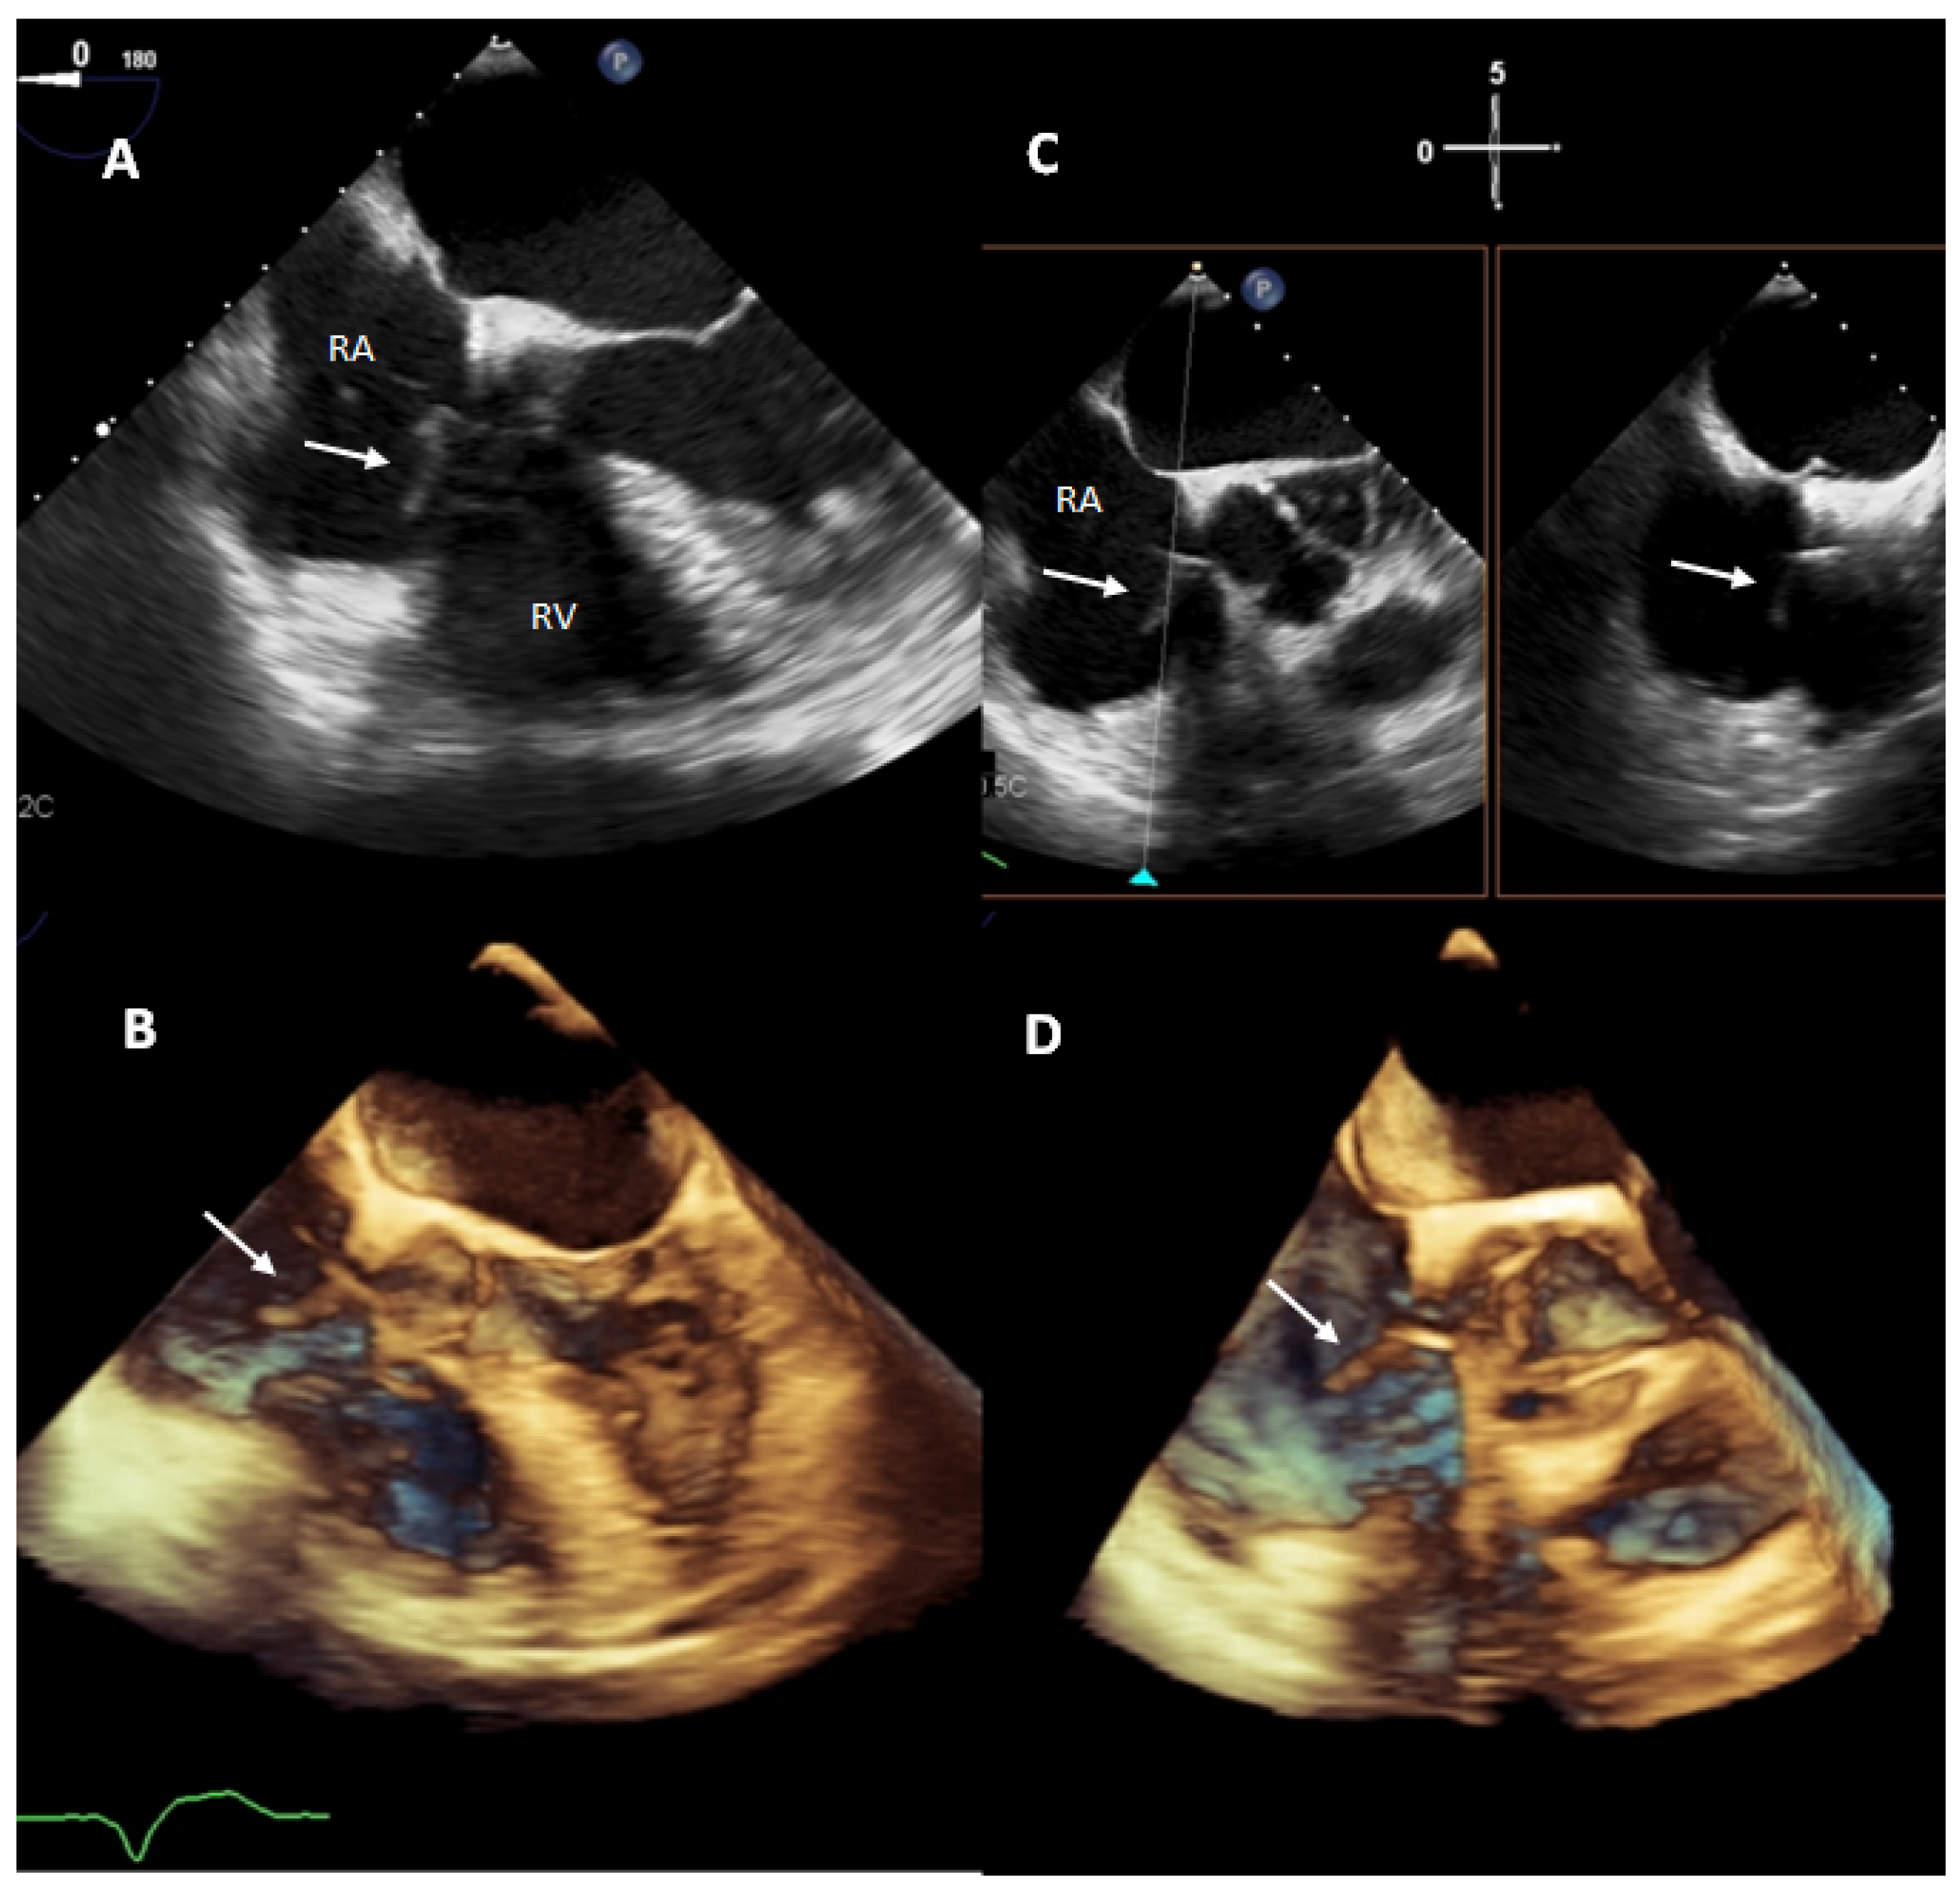

- Downey, B.C.; Juselius, W.E.; Pandian, N.G.; Estes, N.A.M.; Link, M.S. Incidence and Significance of Pacemaker and Implantable Cardioverter-Defibrillator Lead Masses Discovered during Transesophageal Echocardiography. PACE-Pacing Clin. Electrophysiol. 2011, 34, 679–683. [Google Scholar] [CrossRef] [PubMed]